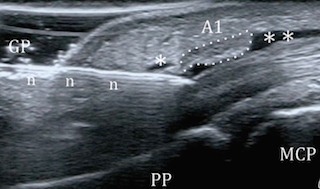

Εικ. διαδικασία επέμβασης και υπερηχογραφική εικόνα

Ο εκτινασσόμενος δάκτυλος (trigger finger) είναι μια συχνή πάθηση σε ανθρώπους που κάνουν επαναλαμβανόμενη κάμψη (λύγισμα) των δακτύλων. Οι τένοντες που κάνουν αυτή την κίνηση σε κάθε δάκτυλο πορεύονται κάτω από συνδέσμους που τους κρατούν στη θέση τους. Σε έναν από αυτούς τους συνδέσμους (που λέγεται Α1 και βρίσκεται στην παλάμη στη βάση κάθε δακτύλου) λόγω προστριβής προκαλείται φλεγμονή, πάχυνση και δημιουργία τοπικής διόγκωσης στον τένοντα. Έτσι εμφανίζεται πόνος τοπικά σε εκείνο το σημείο αλλά και στην κίνηση του δακτύλου. Χαρακτηριστικό είναι επίσης το αίσθημα «μαγκώματος» του δακτύλου καθώς προσπαθούμε να το κινήσουμε επειδή ο διογκωμένος τένοντας μπλοκάρει στον Α1 σύνδεσμο. Σε σοβαρές περιπτώσεις ο ασθενής για να τεντώσει το δάκτυλο του πρέπει να χρησιμοποιήσει το άλλο του χέρι.

Κάνουμε τοπική αναισθησία , εντοπίζουμε τον σύνδεσμο που πρέπει να απελευθερώσουμε με τον υπέρηχο, εισάγουμε μια ειδική βελόνα και την κατευθύνουμε στον σύνδεσμο, η βελόνα αυτή κόβει τον σύνδεσμο. Η επέμβαση έχει ολοκληρωθεί μέσα σε περίπου 15-20 λεπτά. Τοποθετείται ένας επίδεσμος για 24 ώρες. Ο ασθενής μπορεί να κινήσει το δάκτυλό του άμεσα. Μπορεί να εργασθεί στο γραφείο σε ένα με δύο 24ώρα και να κάνει πιο απαιτητική εργασία σε λίγες ημέρες.